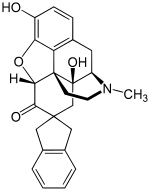

Oripavine derivatives

Thienorphine

- 7-PET

- Acetorphine

- Alletorphine (N-allyl-noretorphine)

- BU-48

- Buprenorphine

- Buprenorphine-3-glucuronide

- Cyprenorphine

- Dihydroetorphine

- Etorphine

- Homprenorphine

- 18,19-Dehydrobuprenorphine (HS-599)

- N-cyclopropylmethylnoretorphine

- Nepenthone

- Norbuprenorphine

- Norbuprenorphine-3-glucuronide

- Thevinone

- Thienorphine

Structures

| Oripavine derivatives | ||||

|---|---|---|---|---|

7-PET 7-PET |

Acetorphine Acetorphine |

Alletorphine Alletorphine |

BU-48 BU-48 |

Buprenorphine Buprenorphine |

Cyprenorphine Cyprenorphine |

Dihydroetorphine Dihydroetorphine |

Etorphine Etorphine |

Homprenorphine Homprenorphine |

18,19-Dehydrobuprenorphine 18,19-Dehydrobuprenorphine |

N-cyclopropylmethylnoretorphine N-cyclopropylmethylnoretorphine |

Nepenthone Nepenthone |

Norbuprenorphine Norbuprenorphine |

Thevinone Thevinone |

Thienorphine Thienorphine |